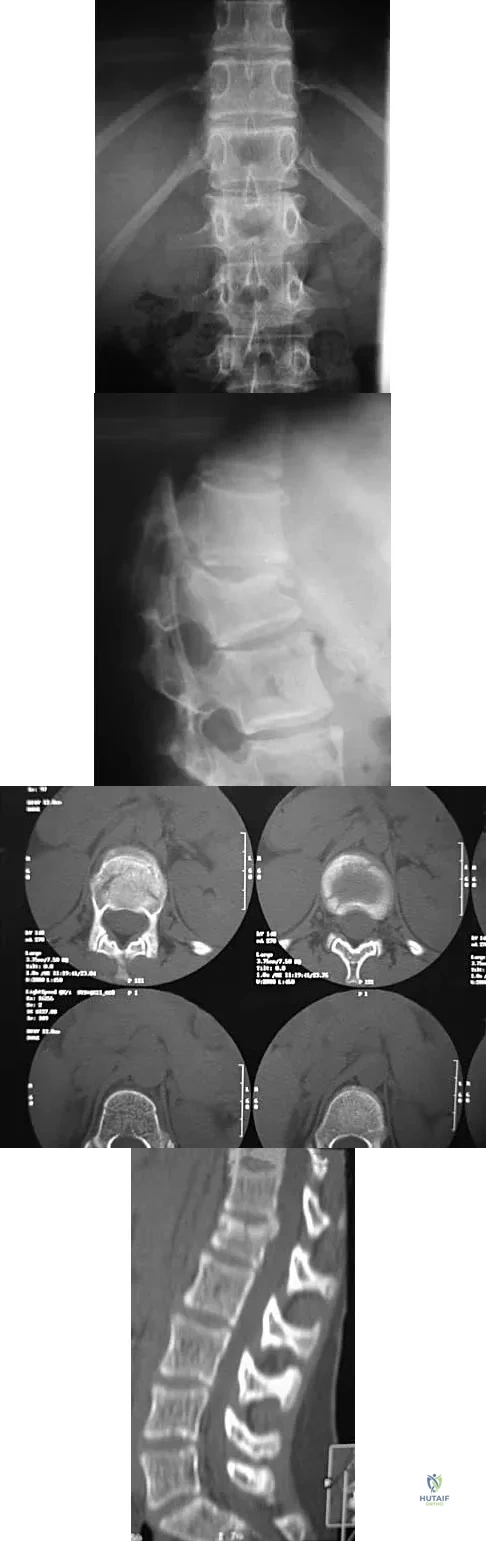

Figure 22 reveals what anatomic variant of the lumbar spine?

A 33-year-old woman sustains a C6 burst fracture diving into a swimming pool, resulting in a complete spinal cord injury. The canal compromise is shown in Figures 8a and 8b. Functional recovery would be maximized with